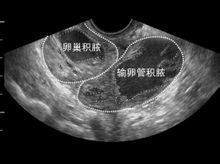

孕囊不規則孕囊只在懷孕早期見到。它的大小,在孕1.5個月時直徑約2厘米,2.5個月時約5厘米為正常。孕囊位置在子宮的宮底、前壁、後壁、上部、中部都屬正常;形態圓形、橢圓形、清晰為正常;如孕囊為不規則形、模糊,且位置在下部,孕婦同時有腹痛或陰道流血時,可能要流產。原因

孕囊不規則是多原因造成的,遺傳、基因、精液抗體、內分泌失調、畸形等等,而這些因素中,只有內分泌失調造成了激素分泌紊亂,是可以通過保胎繼續受孕的。